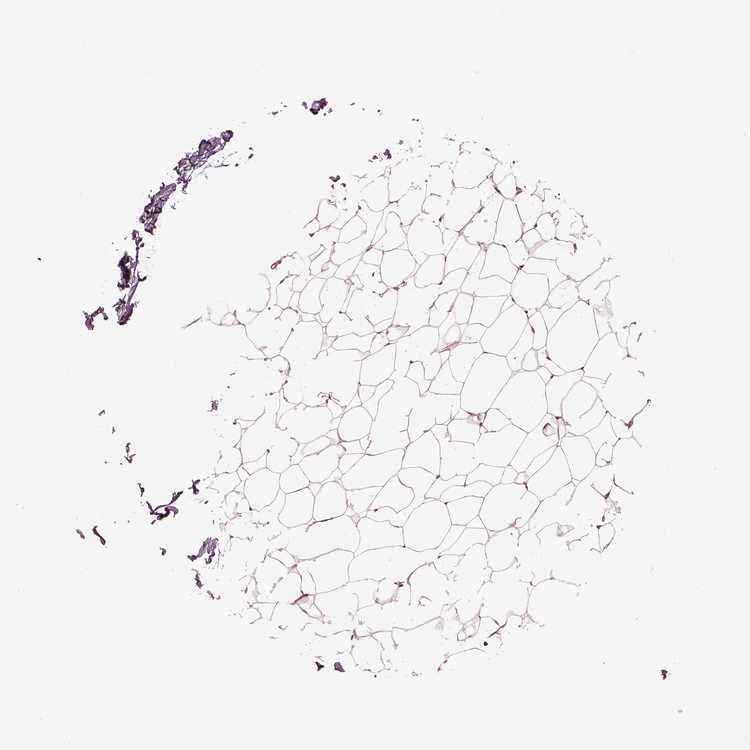

BREAST - HPA RNA-seqi

The RNA-seq details section shows detailed information about the individual samples used for the transcript profiling and results of the RNA-seq analysis.

Information about each individual sample is listed below, including gender, age, a tissue section image and estimated fractions of cell types. nTPM (normalized transcripts per million) values give a quantification of the gene abundance which is comparable between different genes and samples.

Female, age 52

Breast sample 373

nTPM: 30.5

Cell types%

Glandular cells:

15

Adipocytes:

5

Other cell types:

80